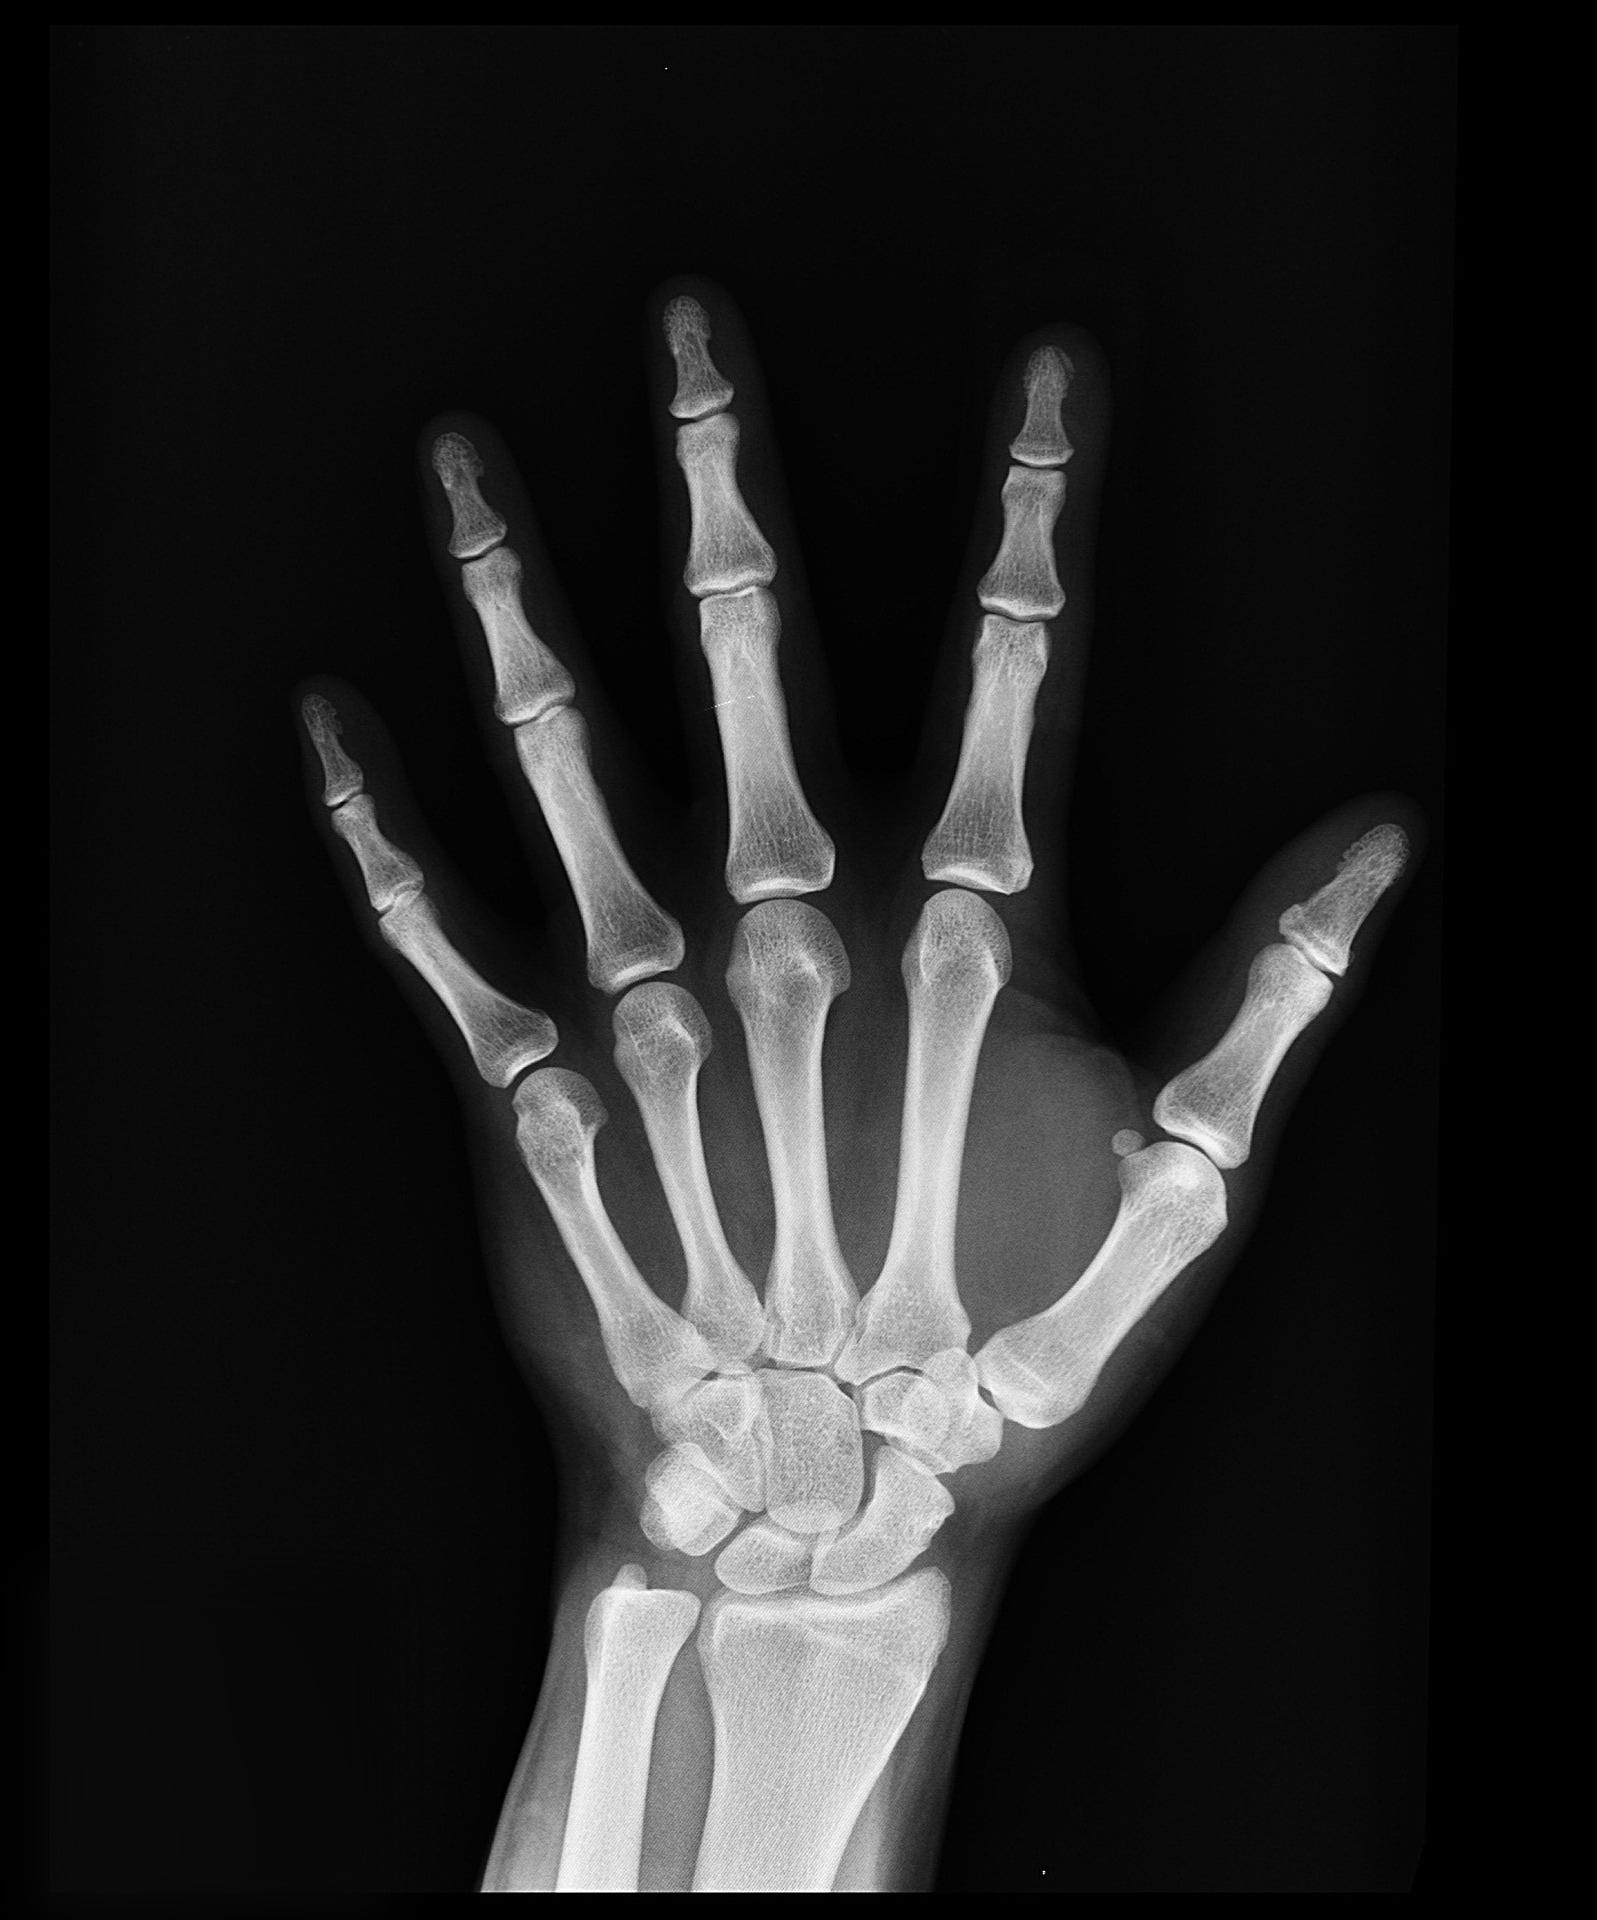

淺談骨齡攝影檢查 Bone Age Study 作者 臺大醫院影像醫學部蔡青華醫事放射師兒童專欄13年11月臺大醫院健康電子報

健康壹點通 掌握骨齡長高當隊長

新學期 新 高度 怎樣才會長高 為什麼有人要去照骨齡 孩子的身高向來是家長關心的議題 一個學期過去了 孩子有長高嗎 長高了多少 不少家 By 安普騰

人體實驗室 小孩是否還會長高 測骨齡照生長板 亞東高銓宏 黃晴 Youtube